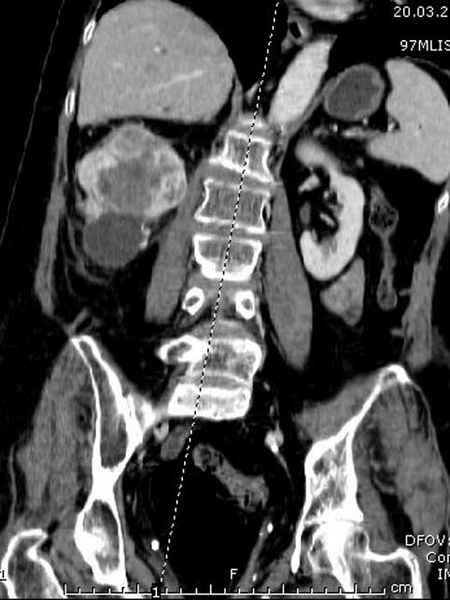

Со слов, больная ничем не болела, только последние 3 месяцев чувствовала боли в бедренной области. КТ брюшной полости подтвердил увеличенную правую почку. (5-6)

Для предупреждения кровотечения во время рассверливания, за день до операции провели эмболизацию сосудов питающий метастаз. http://radiology.rsnajnls.org/cgi/reprint/150/3/673.pdf (7-11, 12-15-16)